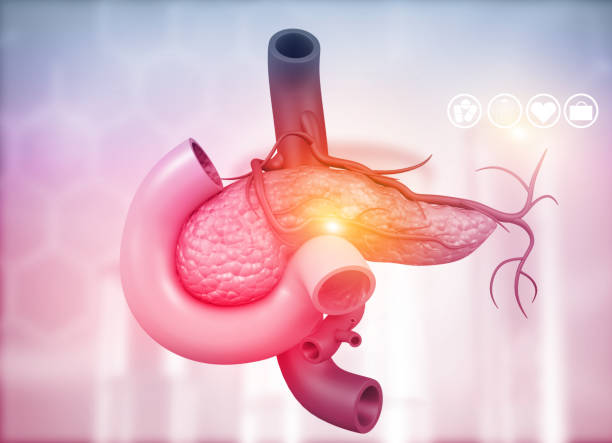

췌장암 초기증상 3. 황달

췌장암 초기증상 두 번째는 황달인데요. 황달은 췌장 머리(췌장 머리)에 암이 발생할 때 대부분의 환자에서 발생해요. 실제로 췌장암 진단을 받은 환자 중 황달로 췌장암을 발견해서 진단을 받는 사례가 많아요.